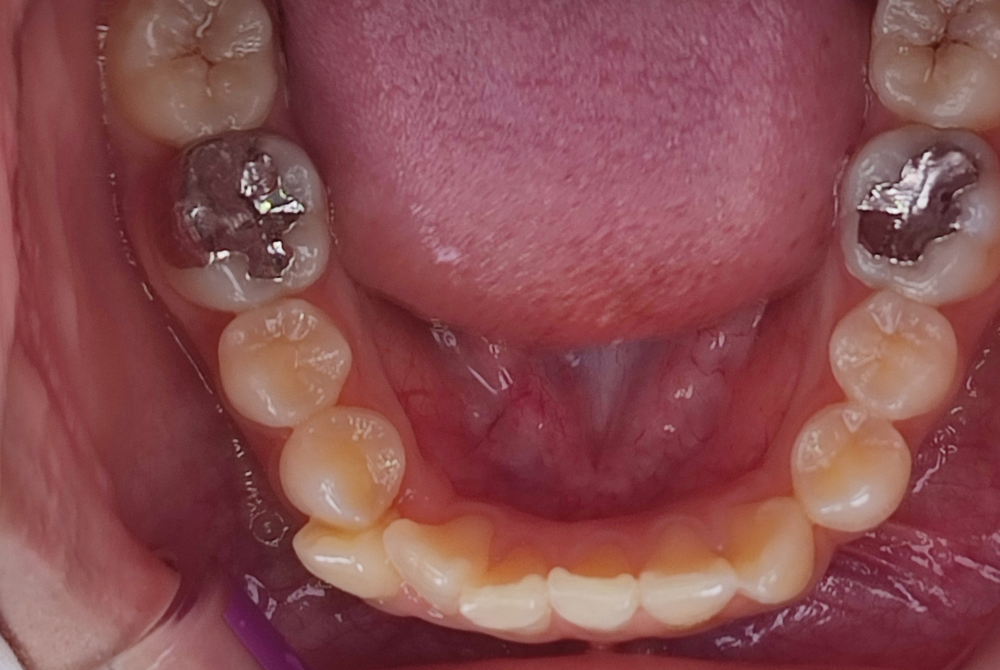

治療後

| 治療名称 | lisiブロッククラウンset(高強度セラミック) |

| 年齢・性別 | 20歳・女性 |

| 主訴 | 銀歯の中に二次カリエス。痛み有、虫歯の処置を希望 |

| 期間 | 1カ月 |

| 費用 | 55,000円(モニター価格) |

| 治療内容 | レントゲン、CTにより、う蝕の進行を説明後、治療を開始。右下6番 窩洞の大きいう蝕(C3)、根管治療、根管充填後、コア築造同日lisiblockセラミッククラウンをセット。 治療結果:見た目はほとんど天然歯と同様で、噛み合わせも調整し、正しい位置で噛めるようになる。セラミックなので傷が付きづらく、ツルツルとしており、歯垢(プラーク)も付着しづらい、接着強度も高く、細菌の侵入を防ぎ、2次カリエスも少ない。 |

| 治療に伴うリスク | 硬い素材ではあるが、噛み方や噛む強さにより、欠けたり割れたりすることがある。 |